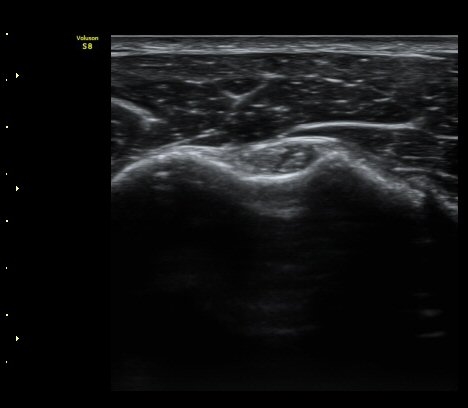

±Ø»ó°Ç ¿ÜÃø Á¾´Ü¸é°Ë»ç¿¡¼­ ±Ø»ó°Ç ºÎÂøºÎ Àú¿¡ÄÚ °á¼Õ°ú ´ë°áÀýÀÇ ºÒ±ÔÄ¢º¯È­°¡ °üÂûµÊ(»çÁø 5)

±Ø»ó°Ç ±ÙÀ§ºÎ Ⱦ´Ü¸é°Ë»ç¿¡¼­ ±Ø»ê°Ç ¿ÜÃøºÎÀÇ Àú¿¡ÄÚ ºÎÁ¾ÀÌ °üÂûµÇ°í(»çÁø 6)